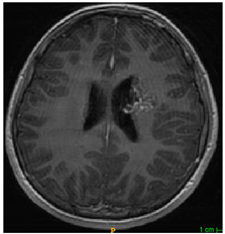

Three cases from the NTUH dataset showing representative results of different models were shown in Table 2, Table 3 and Table 4. The overall dice scores of these networks on the NTUH dataset ranged from 0.33 (DeepMedic) to 0.51 (V-Net). Table 5 shows the detailed performance of each network tested with the NTUH dataset.

Table 3. Predictions with average dice scores.

Ground truthDeconvNetDeepMedic

Applsci 11 09180 i007 Applsci 11 09180 i008 Applsci 11 09180 i009

PSPNetU-NetV-Net

Applsci 11 09180 i010 Applsci 11 09180 i011 Applsci 11 09180 i012